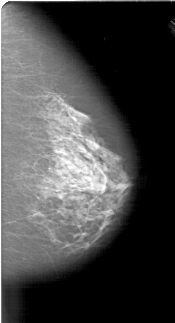

A_1913_1.LEFT_MLO

LEFT_MLO LINES 6481 PIXELS_PER_LINE 3796 BITS_PER_PIXEL 12 RESOLUTION 43.5 OVERLAY